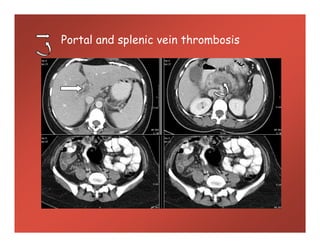

Portal and splenic vein thrombosis